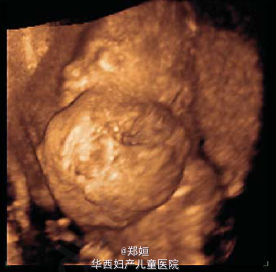

19岁初产妇,孕18周因超声提示胎儿异常就诊

超声和多普勒提示胎儿颈部有一无血流的复杂性多囊肿块 羊膜腔穿刺和流式细胞学均提示无遗传学异常